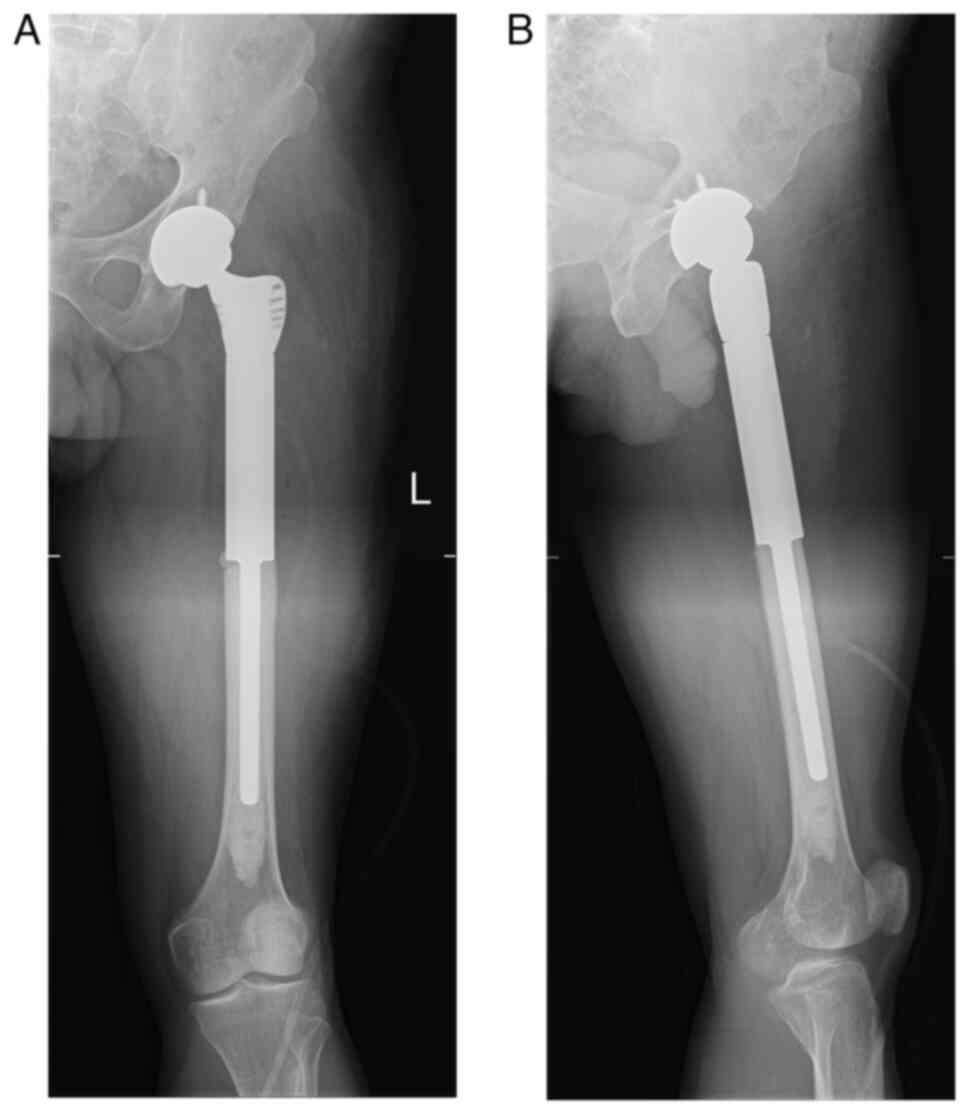

Malignant transformation of an aneurysmal bone cyst of the femoral neck: A case report

Aneurysmal bone cyst (ABC) is a benign, distending, osteolytic and locally aggressive bone tumor that is mostly associated with trauma. Approximately 1% of bone tumors are ABCs, which are most prevalent in adolescents and are usually detected in the spine and long tubular bones. The diagnosis of ABC mainly relies on histopathology, malignant transformation is rare, and the chance of malignancy increases if there are multiple recurrences. Due to the rarity of reports of malignant transformation of ABCs into osteosarcoma, there is still considerable debate on the appropriate treatment strategy. The current paper presents a case of aneurysmal bone cyst malignant to osteosarcoma and the therapeutic measures to provide expertise for the diagnosis and treatment of ABCs that are malignant to osteosarcoma.